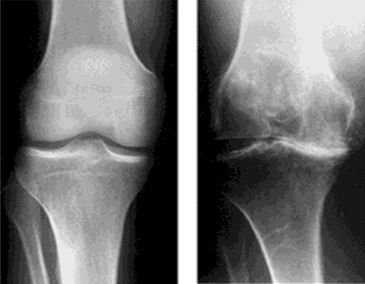

Osteoartritte yaygın patolojik değişiklikler, eklem bağ dokusunda, özellikle de eklem, subkondral kemik, eklem sıvısı ve kapsülde saptanır. Başlıca olay eklem kıkırdağındaki ilerleyici kayıptır ve buna, eklem sıvısındaki hyolünirik asidin muhteviyatının bozulması, eklem çevresindeki kemiklerin yapılarının bozulması küçük yeni kemik çıkıntılarının oluşumu eşlik eder.

1. Diz eklemi: Şişman kadınlarda daha sık görülür. İleri dönemlerde eklem eğrilir. O-bacak ortaya çıkar.